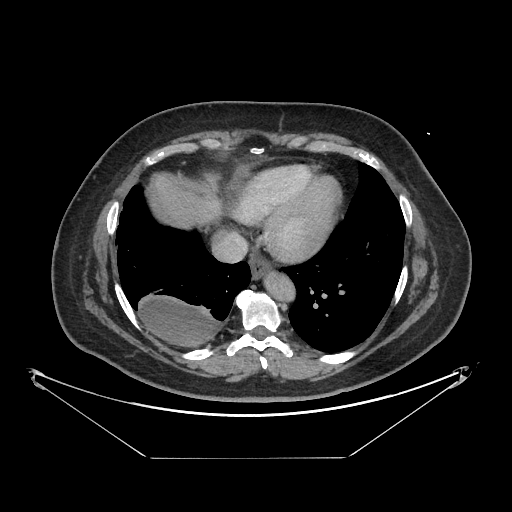

Original VENOUS CT scan

Full window (WL 1023.5, WW 4095 β†’ Low βˆ’1024, High +3071)

Actual HU range: [-160.0, 240.0]

Lung window (WL -600, WW 1500 β†’ Low βˆ’1350, High +150)

Actual HU range: [-160.0, 150.0]

Mediastinum window (WL 40, WW 400 β†’ Low βˆ’160, High +240)